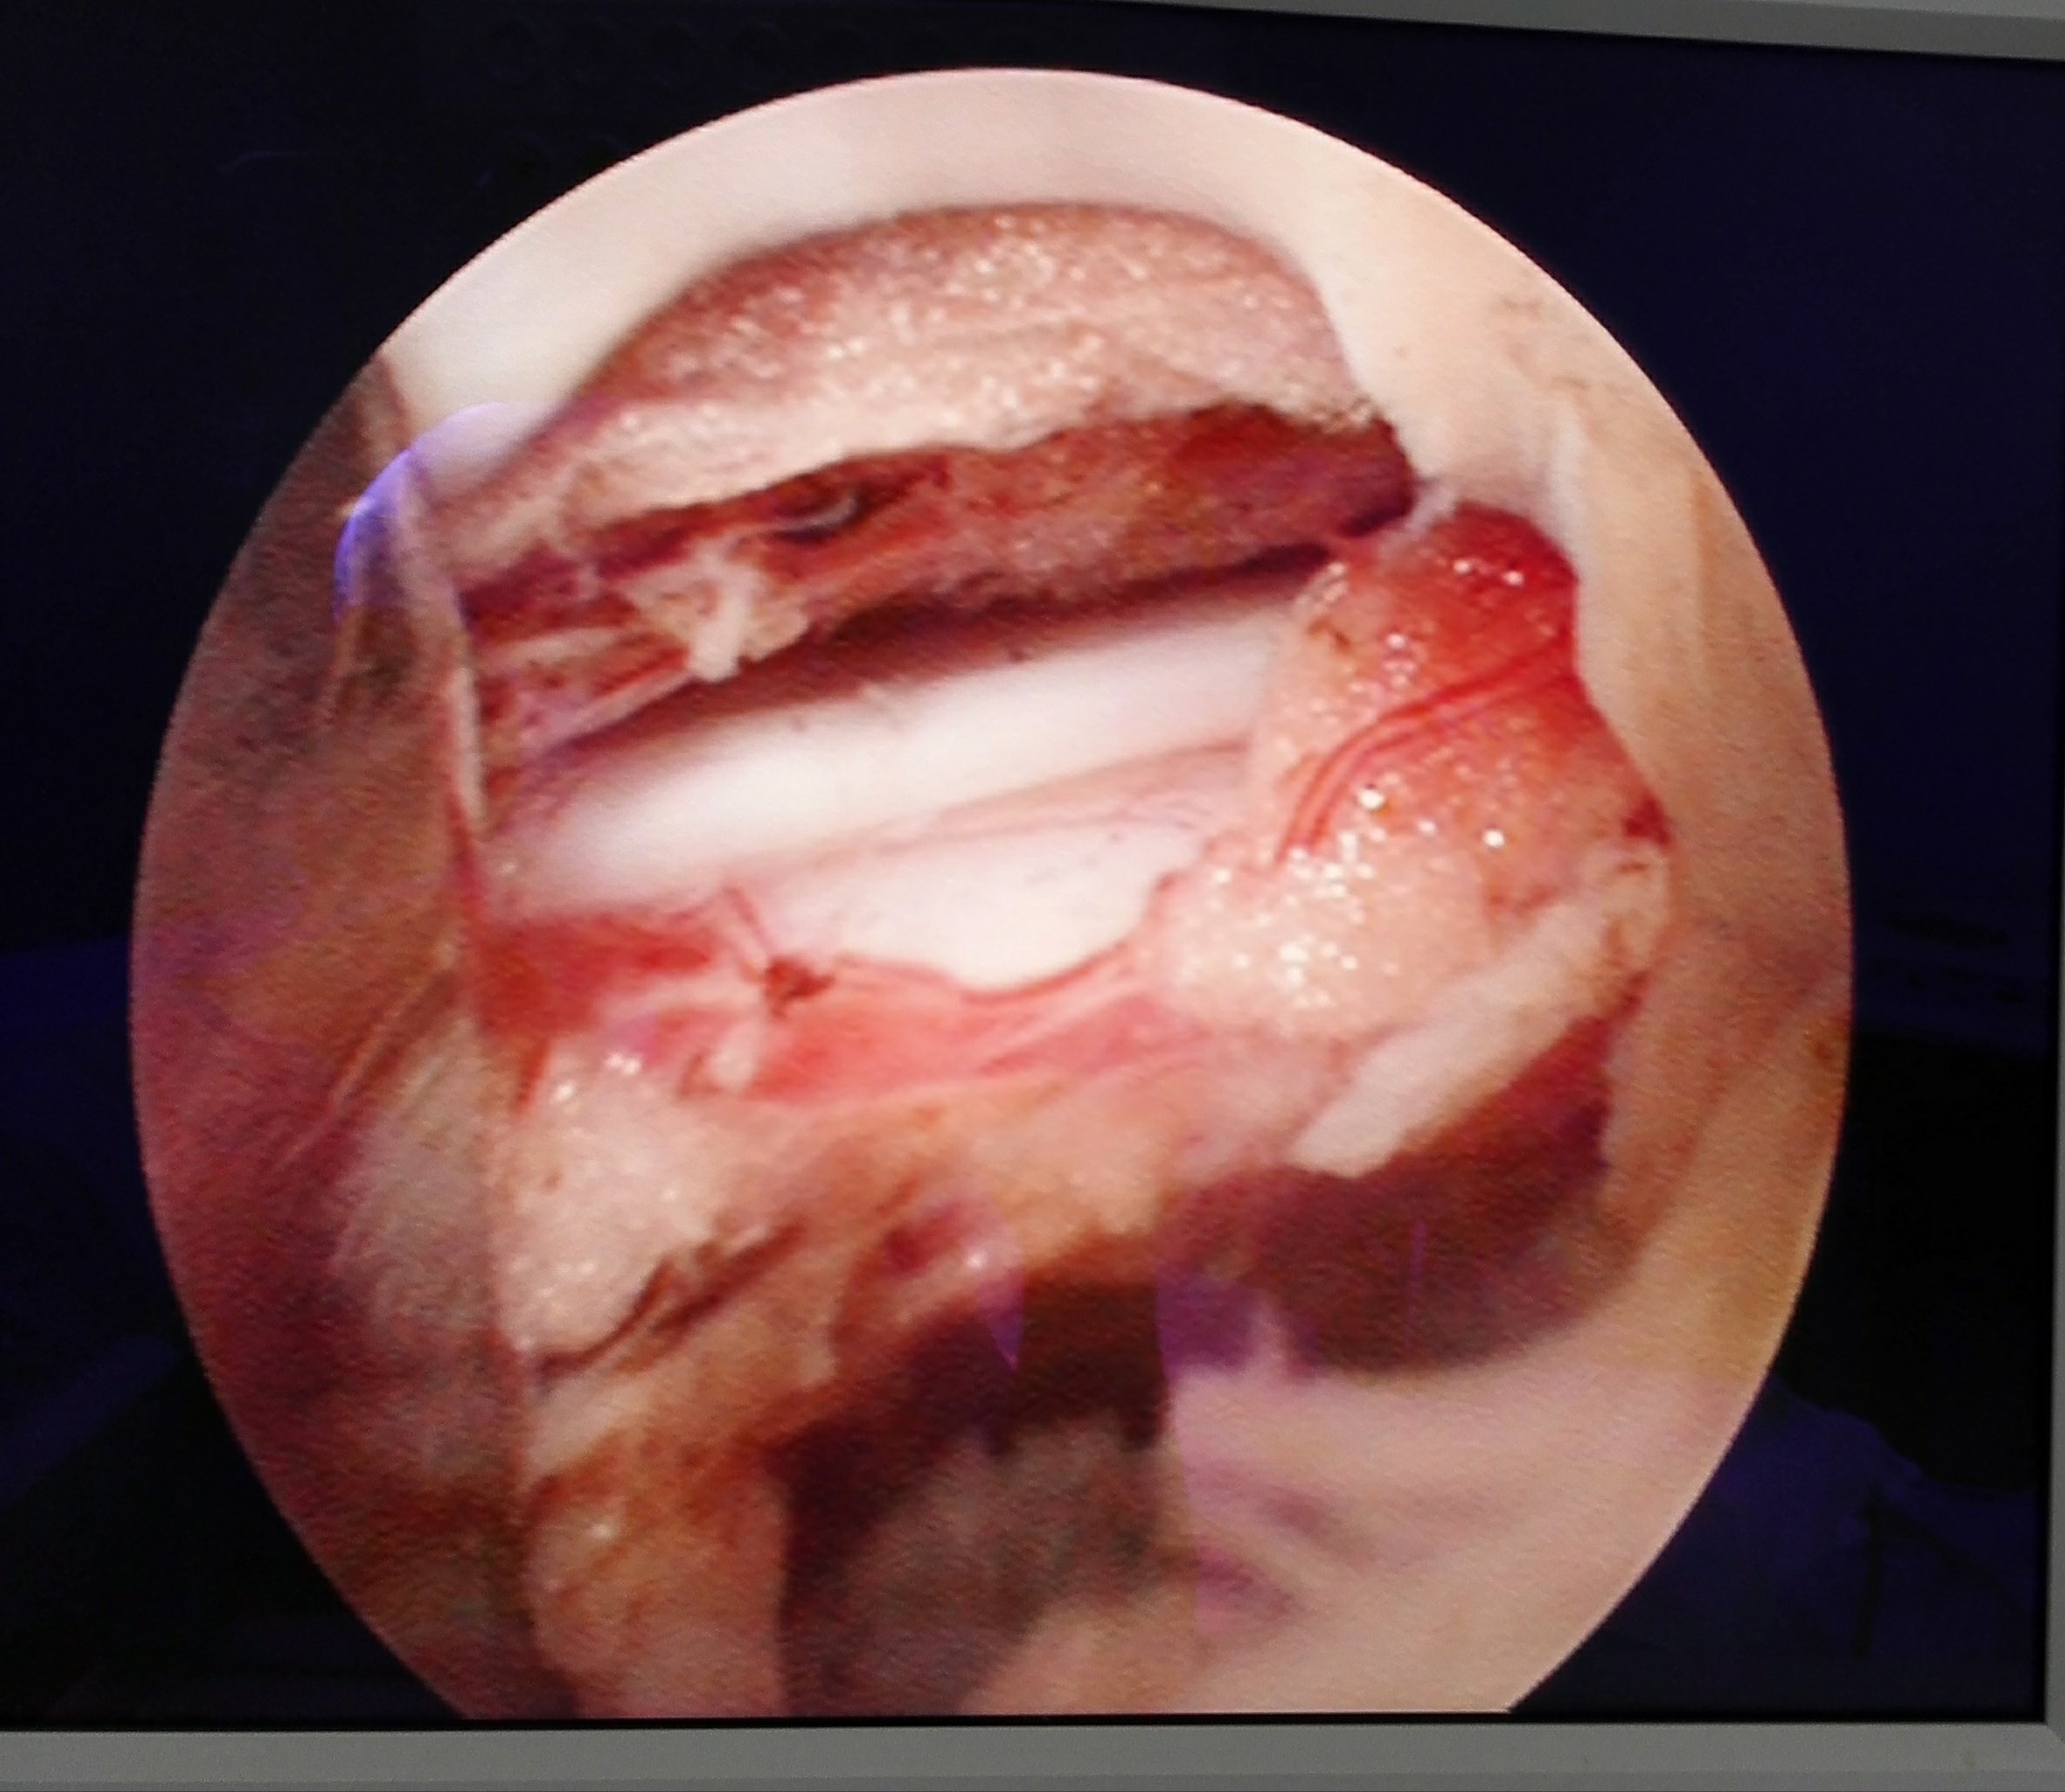

腰椎间盘突出症,微创椎间孔镜间盘摘除术!

腰椎间盘突出症最微创的手术方法--椎间孔镜手